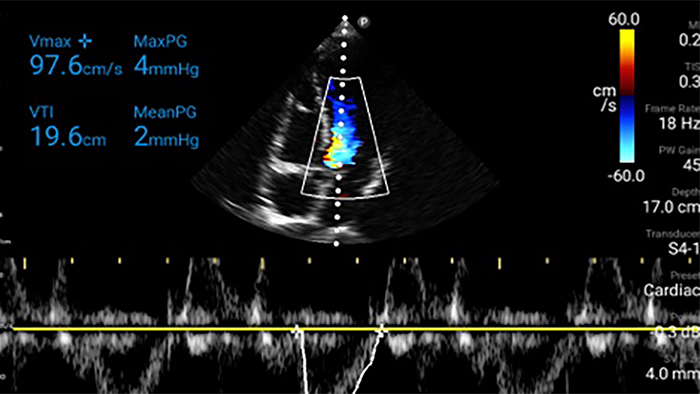

Actúe más rápido para proteger el corazón de sus pacientes

Cuando los segundos cuentan, el ultrasonido portátil puede marcar la diferencia. Lumify puede proporcionar las imágenes de alta definición que requiere cuando y donde las necesite.

Transductor de disposición en fase de banda ancha Lumify S4-1

Oportunidad de revertir potencialmente la miocardiopatía

Introducción a la ecocardiografía transtorácica